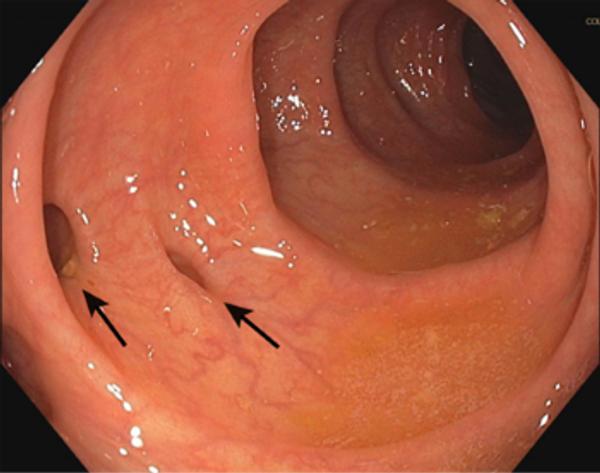

Leestijd: 7 minutenBei einem Divertikel handelt es sich um eine gutartige Ausstülpung der Darmwand in Form eines beutelartigen Gewebes. Diese Ausstülpung ist in der Regel das Ergebnis einer Schwäche der Darmwand, die sich aufgrund des erhöhten Drucks im Darm auswölbt. Eine Hauptursache für die Entstehung eines oder mehrerer Divertikel ist wahrscheinlich eine nicht ausreichende Zufuhr von Ballaststoffen, wodurch sich der Stuhlgang nicht mehr so gut durch den Darm bewegt.

Besonders in höherem Alter leiden viele Menschen an mehreren Divertikeln im Darm, bemerken sie aber kaum, weil sie keine Beschwerden verursachen. Sie werden daher oft zufällig entdeckt. Das Vorhandensein mehrerer Divertikel wird auch als Divertikulose bezeichnet.

Wenn sich ein Patient mit (einigen) der oben genannten Symptome bei seinem Hausarzt vorstellt, wird in der Regel zunächst eine Blutuntersuchung auf Entzündungswerte durchgeführt. Oft wird auch eine Überweisung für eine Ultraschalluntersuchung des Unterbauchs ausgestellt. Bei dieser Untersuchung wird der Dickdarm mit Hilfe von Radiowellen abgebildet, und eventuelle Entzündungen werden sichtbar. Manchmal ist es jedoch nicht klar, dass es sich um eine Divertikulitis handelt, und eine CT-Untersuchung und/oder eine Koloskopie (Untersuchung des Darms durch den Anus mit einem flexiblen Schlauch, der eine Kamera enthält) sind notwendig, um eine genaue Diagnose zu stellen.